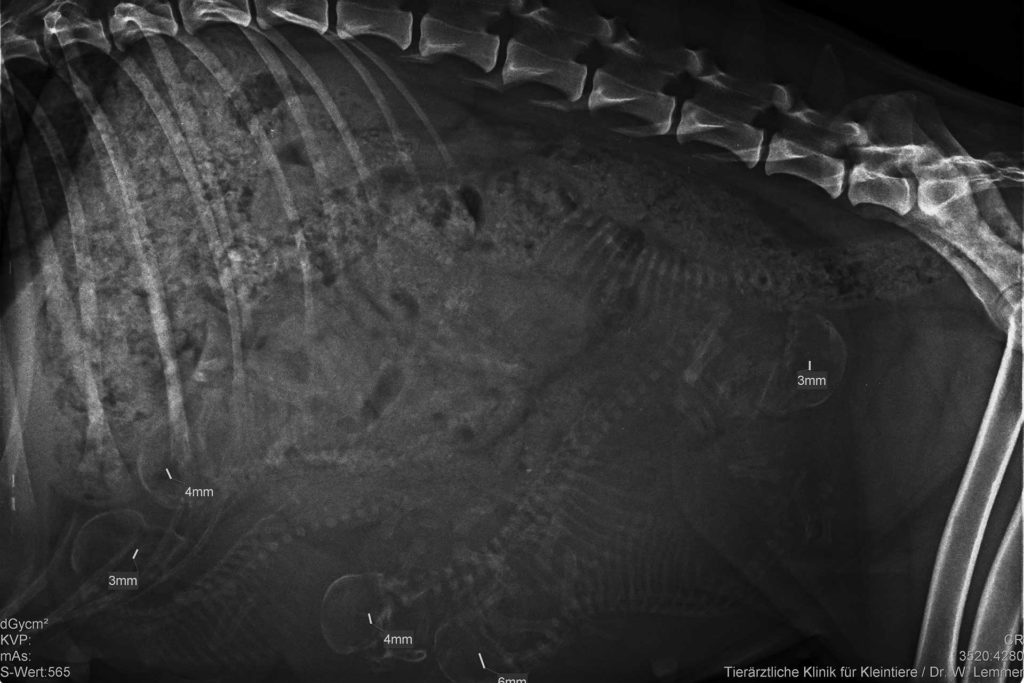

Da beim Ultraschall-Termin am Dreikönigstag nicht sicher festzustellen war, ob sich 5 oder 6 Welpen in Kiras Bauch entwickelten, und Kira inzwischen ganz schön rund geworden ist (27 kg!) haben wir in der vorletzten Woche der Trächtigkeit in unserer Tierklinik eine Röntgenaufnahme machen lassen. Fazit: Es sind 5 quicklebendige Kerlchen, […]